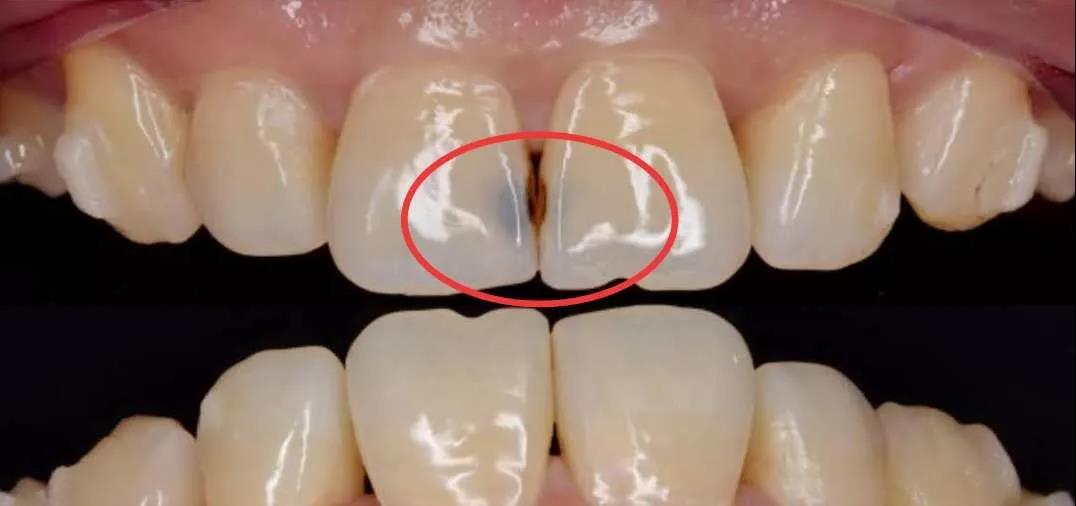

红圈内就是邻面龋

就比如邻面龋,它是发生在两颗牙齿相邻的区域的一种被蛀情况,因为牙刷清洁不到一部分牙缝,久之细菌在其间繁殖就致龋了。

预防邻面龋,需要使用牙线清洁牙缝间的食物残渣和细菌。

所以,仅仅只窝沟封闭,就能够完全预防蛀牙,是不可能的。